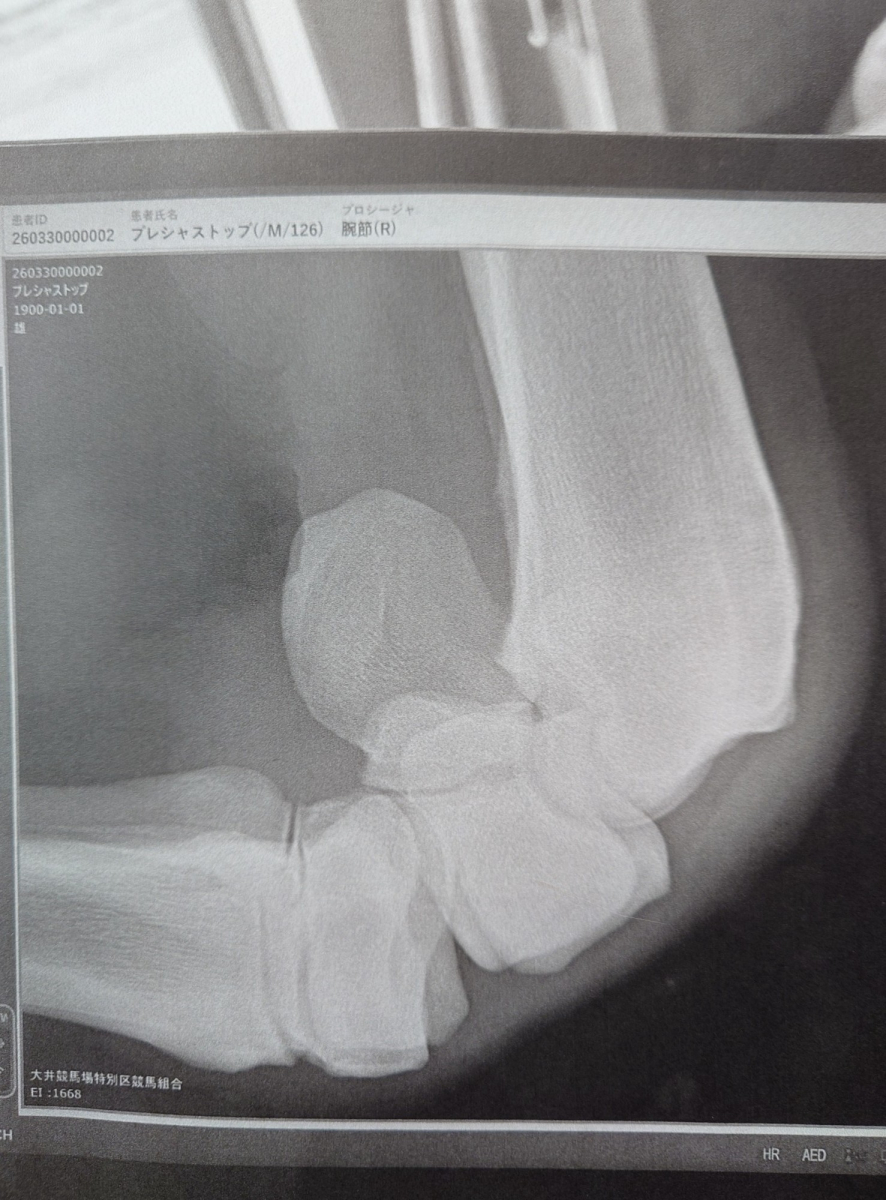

本馬は2025年2月2日に東京ダート1600mの3歳新馬戦でデビュー。中団待機からラストはメンバー最速の上がりタイムをマークして猛追し、0秒1差の3着まで追い上げました。2戦目の中山ダート1800m戦では果敢に先行しましたが、早めに後退してしまい11着に大敗。レース中に右前橈骨遠位端骨折を発症していたことが判明し、骨片除去手術を実施。9号見舞金を受給し、この一戦を最後にJRAの登録は抹消。大井へ移籍しています。

ところが、この一戦後に右膝の骨膜剥離が確認されました。勝った直後のタイミングとはなりますが、休養がベストとなったこともあり、頭数整理のためにオークションに出品させていただきます。

【本馬についての現状説明】

右ひざは保存で歩様確認し、競馬を使うことも可能ですが、休養も必要との所見です。また、検査は受けていませんがノドの異音を確認しています。ただ、乗った騎手の話ですと、レースでは影響ない感じとのことでした。(大井競馬小林・坂井英光調教師)

※2025年4月6日の競走で右前橈骨遠位端骨折発症。骨片除去手術を実施。事故見舞金9号(競走中の事故により事故発生の日から6ヵ月以上中央競馬の競走に出走できなくなった場合)を受給しています。